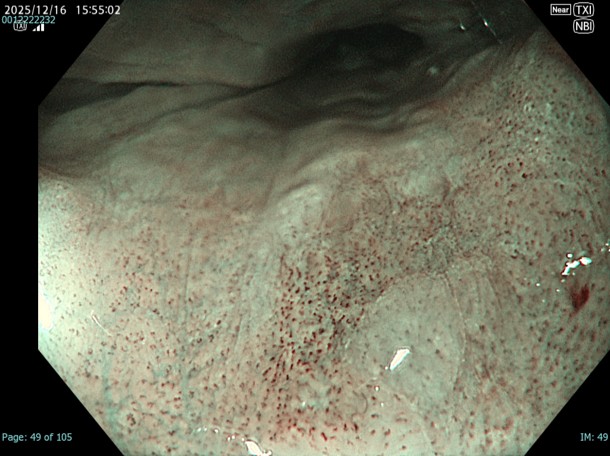

• NBI+TXI観察(近景)

切替前 NBI強調設定:A8

NBI+TXIレベル:高

図8 図7 図9

NBI観察と比較するとDLが明瞭であり、この後行うESDにおいてもマーキングに有用であった。